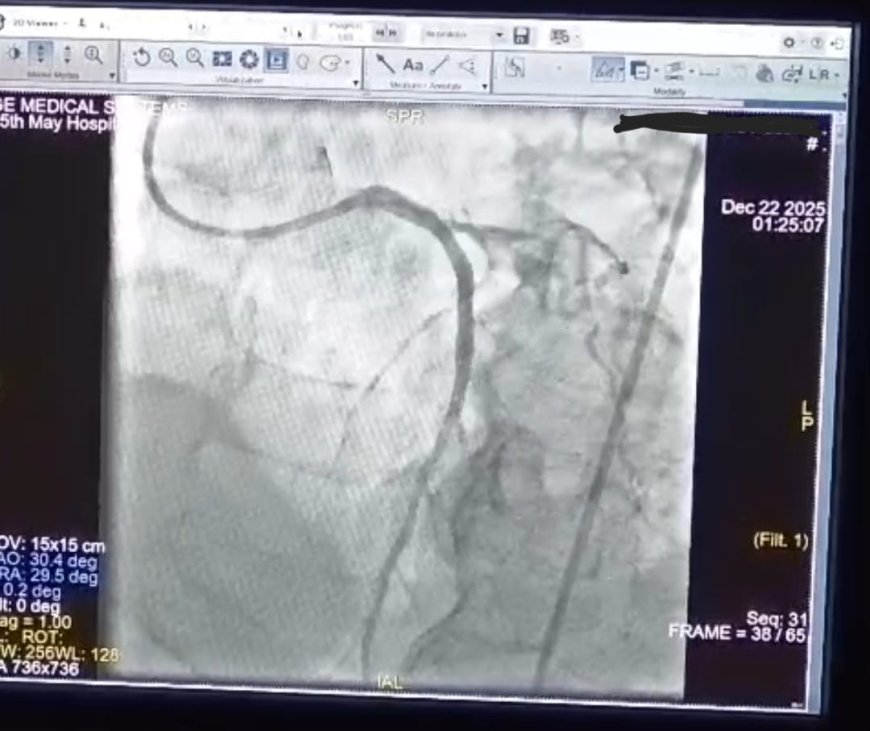

بكل فخر واعتزاز، تُعلن مستشفى ١٥ مايو النموذجي عن إنجاز طبي استثنائي ، نجح قسم القلب، برئاسة الأستاذ الدكتور أحمد جعفر، في إنقاذ حياة مريض كان في حالة حرجة بعد إصابته بـ:

جلطة قلبية حادة مكتملة بالشرايين التاجية نتج عنها توقف بعضلة القلب.

تم على الفور بقسم الطواريء بدأ الانعاش القلبي الرئوي وتركيب انبوبة حنجرية حتى تم استعادة النبض وسرعان ما تم تفعيل بروتوكول القسطرة القلبية الطارئة وتم نقل المريض إلى وحدة القسطرة القلبية وتم إجراء قسطرة لفتح الشريان الرئيسي وتركيب دعامتين دوائيتين.